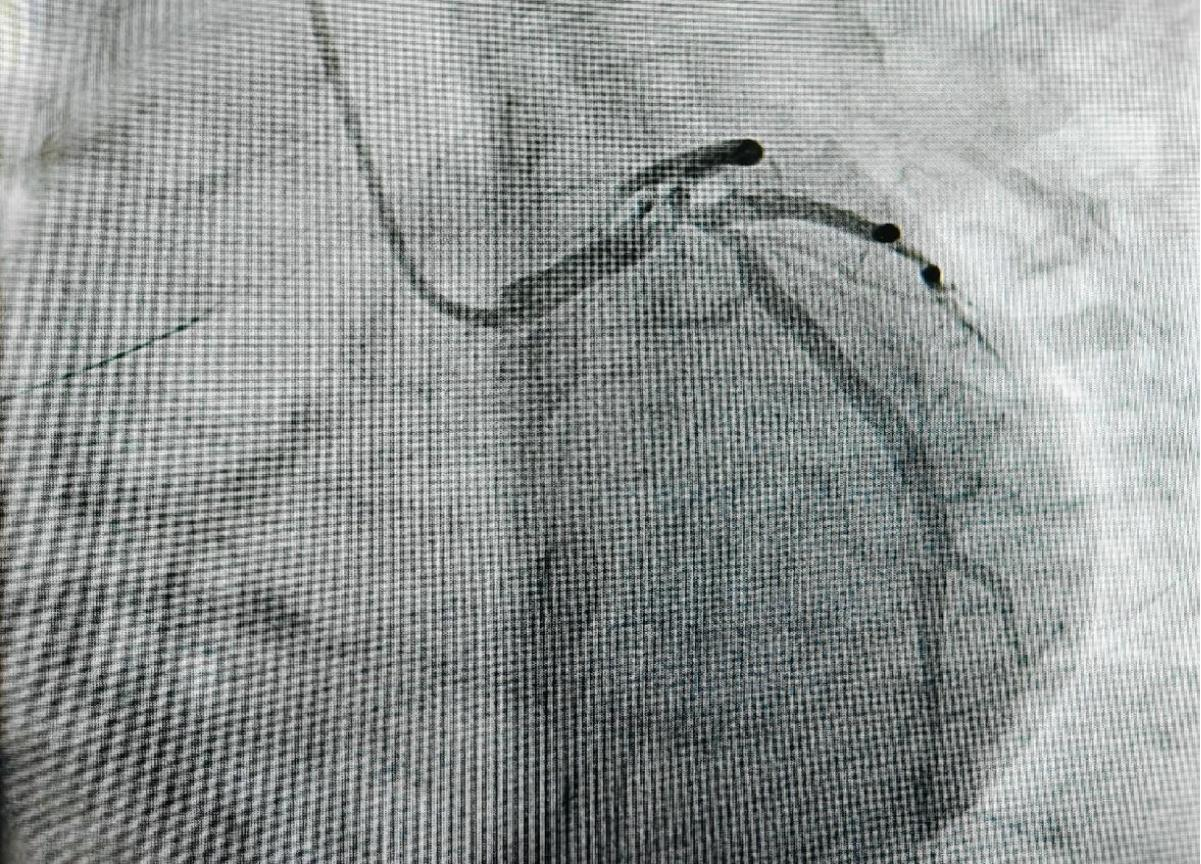

患者最初因胸痛前往当地医院就诊,当地医院通过冠脉造影检查发现,患者左主干末端呈现真性四分叉病变,且多支血管存在严重狭窄的情况,病情十分危急。鉴于患者病情的复杂性,当地医院联系了昆医大附二院,随后患者转入院内进一步治疗。心血管内科楚天舒团队接诊后,立即启动应急响应机制,从决定为患者实施ECMO上机,到成功建立循环支持,仅耗时28分钟,为抢救患者赢得了宝贵时间。本次手术中,手术团队创造性运用主动脉内球囊反搏(IABP)+体外膜肺氧合(ECMO)双循环支持系统(IABP + ECMO), ECMO能够有效确保患者的血液循环稳定, IABP可以减轻心脏负担,改善心肌供血,两者协同配合,大大降低术中心脏骤停的风险,极大地提高了手术的安全性。

手术实施双主刀制度,由心血管内科介入团队与MICU紧密合作,确保循环支持与血运重建同步进行,全方位保障手术的顺利开展。术后,采用目标导向镇静策略,精准管理确保患者在48小时内成功撤除ECMO,有效降低了患者术后并发症。